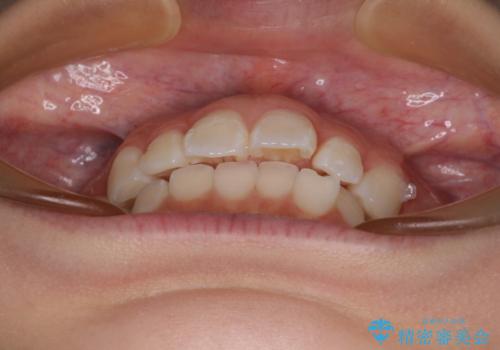

- 上下前歯の叢生を気にして来院された患者様です。

インビザラインでの治療を希望されていて、デコボコの程度が中等度であり、安価なパッケージにて対応可能と判断されたため、インビザライン・モデレートを用いて矯正治療を行うこととしました。

インビザライン・モデレートは、製作できるアライナーの枚数に制限があるため、移動可能な量に限りがあるものの、インビザライン・ライトよりも枚数が多いため、幅広い症例に対応可能です。